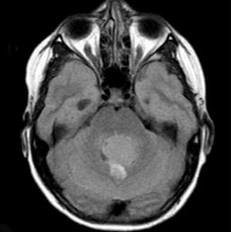

髓母细胞瘤(如图所示)的临床特点()A.高度恶性B.儿童多见C.绝大多数发生于小脑蚓部D.可发生脊髓种植性转移E.对放疗敏感

问题 髓母细胞瘤(如图所示)的临床特点()

选项 A.高度恶性 B.儿童多见 C.绝大多数发生于小脑蚓部 D.可发生脊髓种植性转移 E.对放疗敏感

答案 ABCDE